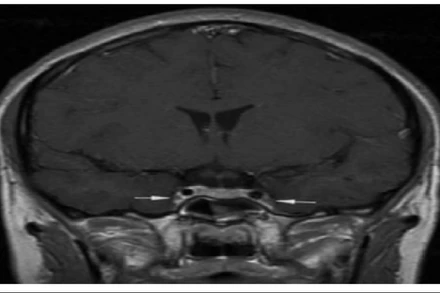

Vị trí mũi tên là viêm và co thắt động mạch cảnh trong 2 bên.

Chỉ với biểu hiện ngạt mũi, sổ mũi, đau đầu nhẹ, bệnh nhân nhanh chóng phải nhập viện với tình trạng co giật, rối loạn ý thức do viêm tắc tĩnh mạch xoang hang - một tình trạng huyết khối nhiễm trùng ở nền sọ. Hiện bệnh nhân vẫn đang trong tình trạng nguy kịch.